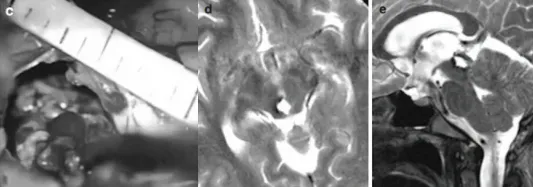

磁共振检查结果很快明确:松果体区存在病变,并发梗塞性脑积水。

女儿爱发呆的表现实为大脑发出的求救信号。情况危急,患儿被迅速推入手术室,必须立即手术以缓解脑积水。实施内镜下第三脑室造瘘术后,关女士才得以暂时松一口气。

松果体为位于大脑中心的红灰色小腺体,大小仅约5-8毫米,却可能发生超过17种不同类型的病变。其解剖位置深在,位于上丘脑,处于两侧大脑半球之间,藏于丘脑连接处的沟槽内,毗邻第三脑室、胼胝体、丘脑等重要结构及关键血管,手术难度极高。

巴教授采用幕下小脑上入路,成功暴露病变区域。术中发现病变为典型的海绵状血管瘤,并伴有新鲜的病灶内出血。最终,巴教授成功将血管瘤完整切除,术中未造成任何并发症。